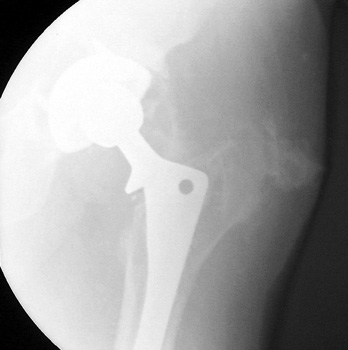

Normal arthrogram